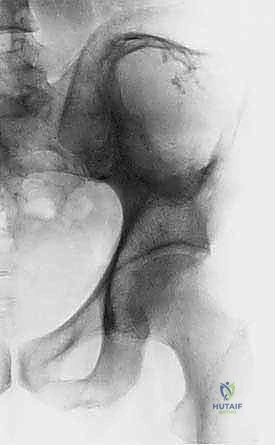

- التصوير بالأشعة السينية (X-rays): الفحص المبدئي لرصد أي تآكل أو تدمير في البنية العظمية للحوض ومفصل الورك.

- أورام الحُق (Acetabulum): هذه هي الحالات الأكثر تعقيداً وإلحاحاً. تدمير سقف الحُق يعني أن رأس عظم الفخذ سيندفع داخل تجويف الحوض عند محاولة المريض الوقوف، مما يسبب ألماً يفوق الوصف وقصراً في الطرف السفلي. تتطلب هذه الحالات خبرة جراحية استثنائية لإعادة بناء التجويف باستخدام الإسمنت العظمي، الدعامات المعدنية، أو المفاصل الصناعية المخصصة (Custom-made Endoprostheses).

- الألم الميكانيكي (عند الحركة): ألم حاد ومفاجئ يظهر عند الوقوف، المشي، أو نقل الوزن على الساق المصابة. هذا المؤشر خطير ويدل غالباً على ضعف شديد في العظم واقترابه من الانكسار (كسر وشيك).

- الكسر المرضي المفاجئ: في بعض الحالات المؤسفة، يكون العرض الأول هو كسر مفاجئ في الحوض ناتج عن حركة بسيطة جداً كالانقلاب في السرير أو التعثر البسيط.

2. الكسور المرضية الحاصلة أو الوشيكة (Impending Fractures)

التقييم البيوميكانيكي هو تخصص دقيق. يستخدم الدكتور هطيف معايير علمية (مثل معايير هارينغتون Harrington Criteria) لتحديد ما إذا كان عظم الحُق أو الحوض على وشك الانهيار.

* الكسر المرضي الفعلي: إذا انكسر الحوض بالفعل، فإن الجراحة ضرورية لتثبيت العظم المكسور والسماح للمريض بالحركة.

* الكسر الوشيك: إذا أظهرت الأشعة المقطعية أن الورم قد دمر أكثر من 50% من قشرة العظم المحيطة بمفصل الورك، أو تسبب في ألم شديد عند تحميل الوزن، فإن التدخل الاستباقي لمنع الكسر أسهل وأكثر نجاحاً من محاولة إصلاح كسر قد حدث بالفعل.